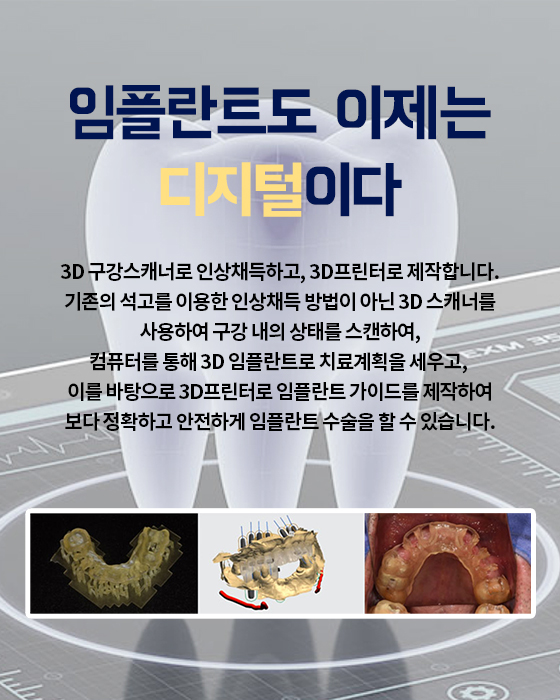

디지털 임플란트

네비게이션 임플란트는 길을 알려주는 네비게이션처럼 치조골의 구조와 신경 위치를 파악하여 정확하게 임플란트를 식립할 수 있는 임플란트 방법을 말합니다.

네비게이션 임플란트는 3D CT를 통해 입체 영상으로 정확한 수술 계획을 세우고, CT자료를 기반으로 구강에 끼우는 보조장치를 제작하여 잇몸 절개없이 작은 구멍을 뚫어 임플란트를 식립하여, 잇몸을 절개하는 수술방법보다 통증과 출혈이 적어 비교적 회복이 빠르게 나타납니다.

네비게이션 임플란트는 3D CT를 통해 입체 영상으로 정확한 수술 계획을 세우고, CT자료를 기반으로 구강에 끼우는 보조장치를 제작하여 잇몸 절개없이 작은 구멍을 뚫어 임플란트를 식립하여, 잇몸을 절개하는 수술방법보다 통증과 출혈이 적어 비교적 회복이 빠르게 나타납니다.